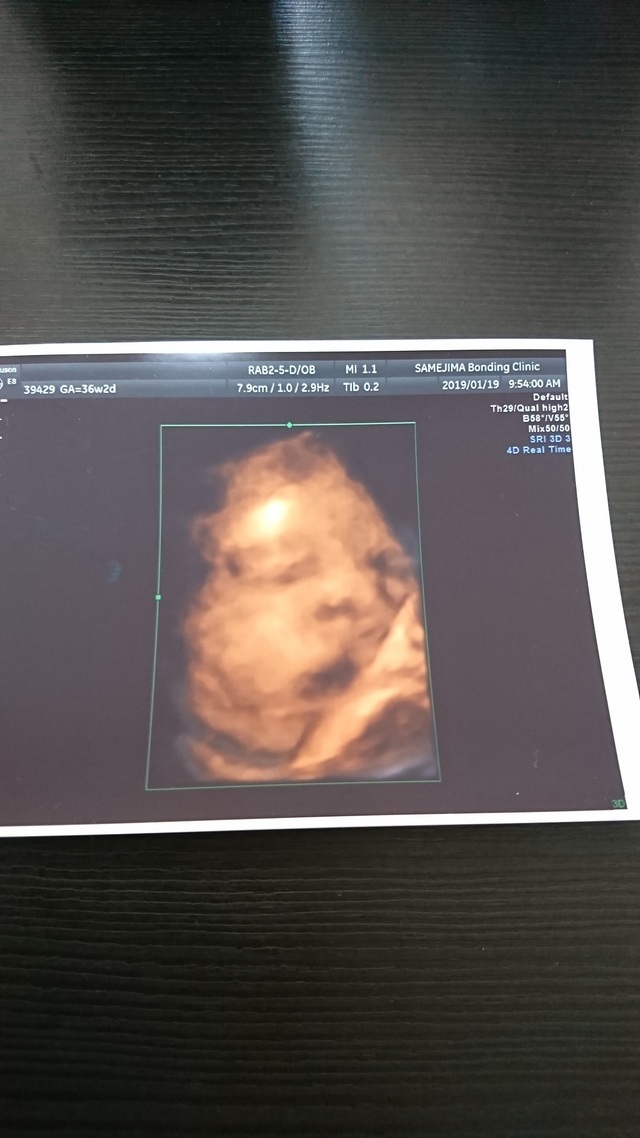

臨月に入ってお腹が重くて何をするのも大変でした。でもお腹の中で元気に暴れまわってるのを感じると、痛みよりももうすぐ会えるんだなーとか胎動を感じられるのもあと少しなんだなーとわくわくして毎日を過ごしていました。この時のエコー写真で初めて正面の顔を見ることができて、パパとあまりにもそっくりだったので両家の家族や共通の友達と大笑いしたのを覚えています。この時点で推定体重が3200gになっていて、初めての出産でこんなに大きい子を無事に普通分娩で産めるのか不安でしたし、体を動かすのは大変な時期でしたが家族に支えられて楽しく毎日を過ごしていました。